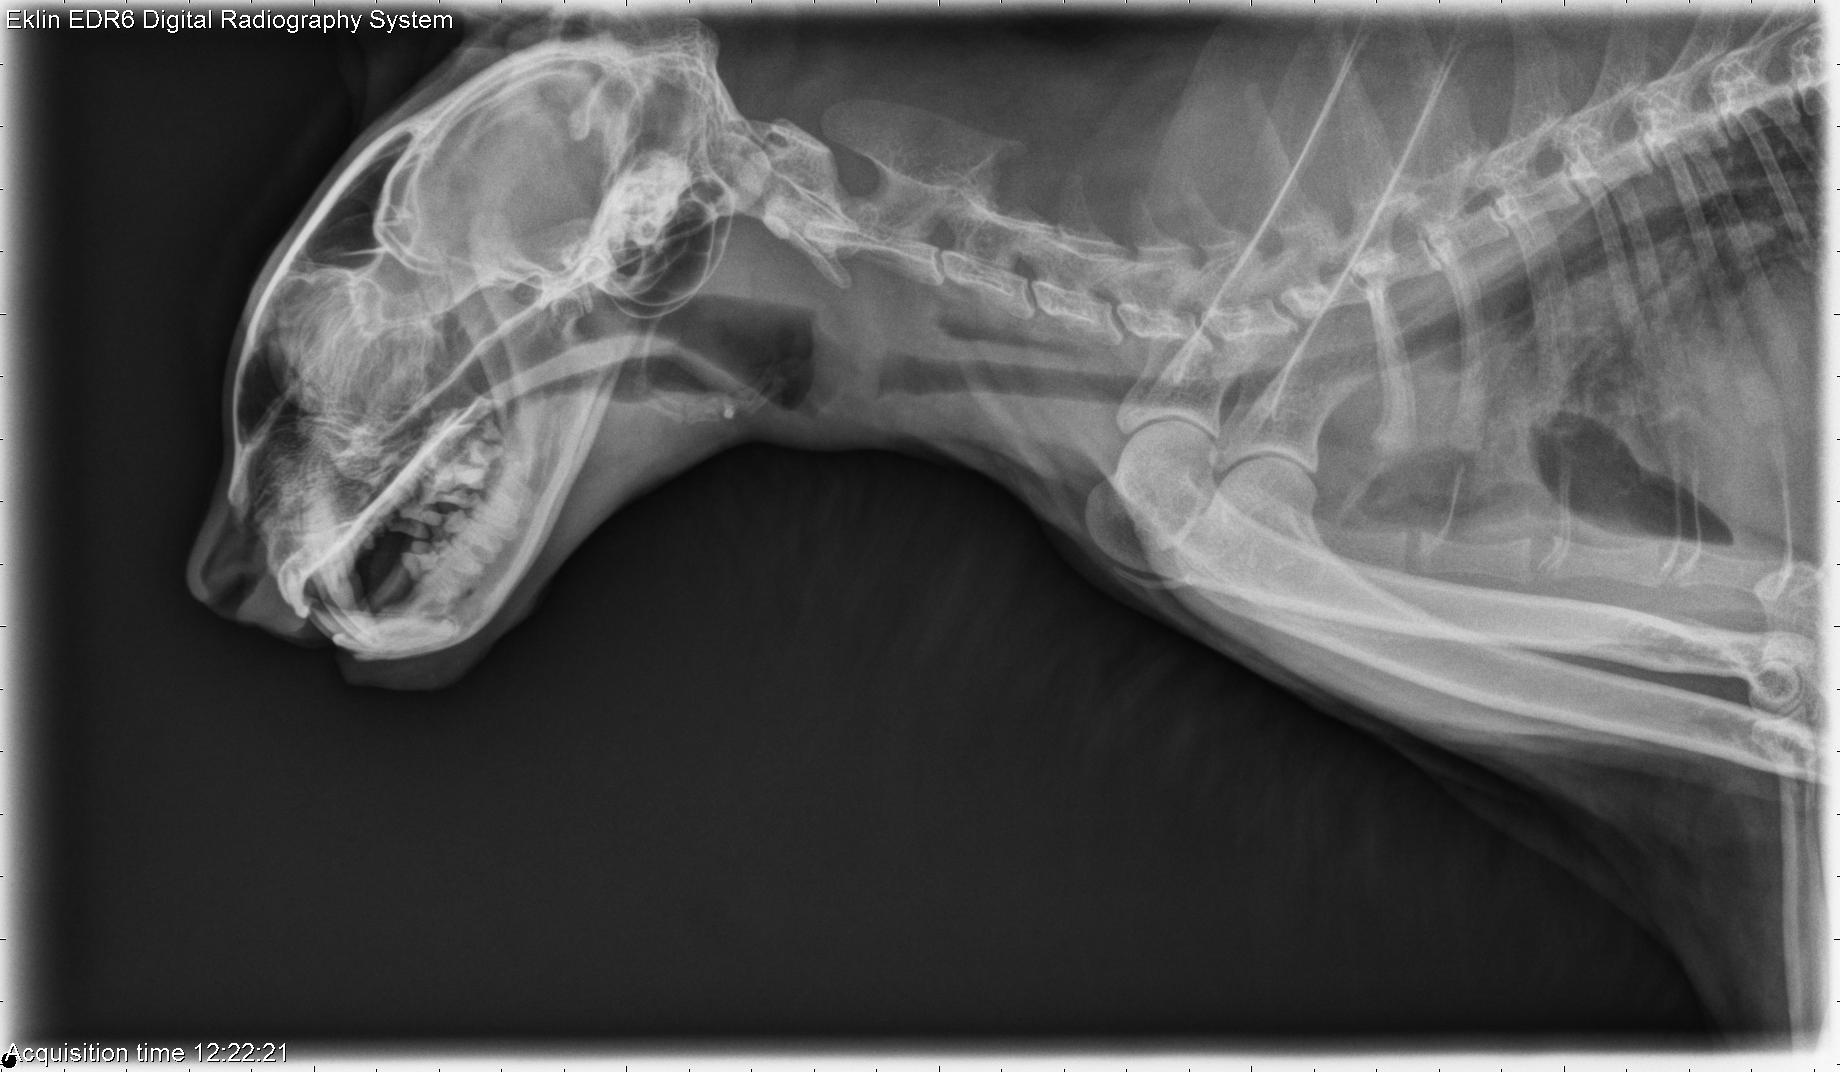

Xray Cat Injured Trachea Stock Photo 673814119 Shutterstock Cat Throat X Ray Lets look at same cat radiographs. Click on them to make them larger. The normal thoracic tracheal diameter in the cat has been reported as 5.5 mm or 18% of the thoracic inlet (20% in normal persian cats). First, we will learn some normal. Chest x‑rays are typically done for cats exhibiting lower respiratory signs, such as cough, rapid shallow. Cat Throat X Ray.